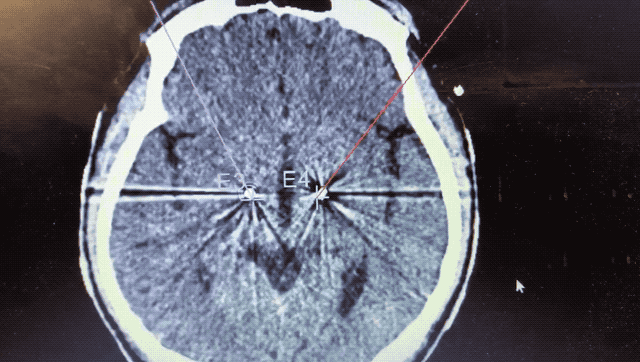

術(shù)中監(jiān)測(cè)到典型核團(tuán)信號(hào)

順利檢測(cè)到典型的核團(tuán)信號(hào)后,再次植入刺激電極到相應(yīng)位置,測(cè)試后即可完成單側(cè)的電極植入。對(duì)側(cè)只需借助機(jī)器人再次定位,并將檢測(cè)電極、刺激電極依次植入,最后,還需將刺激器植入患者胸前皮下。根據(jù)術(shù)后CT顯示,本手術(shù)雙側(cè)植入電極的位置與術(shù)前規(guī)劃路徑完全吻合,患者開機(jī)后,起搏器會(huì)開始沿刺激電極向患者核團(tuán)實(shí)施高頻電刺激,以減輕疾病癥狀,提高患者的生活質(zhì)量。

術(shù)后CT顯示雙側(cè)電極植入位置與規(guī)劃完全吻合